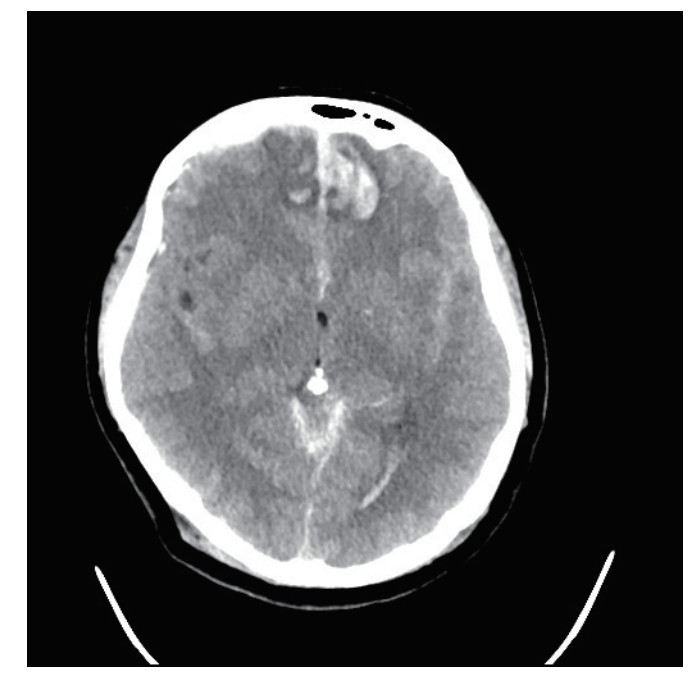

1 病例资料患者,女性,40岁,因“车祸致全身多处外伤半小时余”于2025年6月27日由120送入黄山市人民医院急诊。患者2 h前骑电瓶车发生车祸,致头面部、胸部及左下肢严重受伤,当即昏迷,伴恶心呕吐。入抢救室时自主呼吸微弱,后出现室速,伴随血流动力学不稳定,GCS评分为6分(E1V1M4),双侧瞳孔不等大、对光反射迟钝,左侧直径3 mm,右侧5 mm,后枕部头皮血肿,左下肢胫腓骨区域明显肿胀畸形。医院立即实施全面评估,经紧急行电复律、利多卡因静推后恢复自主心率,予以气管插管保护气道,建立深静脉通路泵入血管活性药物维持血压、纠正酸中毒。完善CT检查:双侧脑挫伤、创伤性蛛网膜下出血、右侧额顶部硬膜下血肿,中颅底及枕骨骨折、累及枕骨大孔,左侧胫腓骨骨折及双肺坠积性改变。见图 1,2。神经外科会诊诊断为弥漫性轴索损伤,无立即手术指征,收入EICU监护稳定生命体征。

| 图 1 脑挫伤伴出血 |